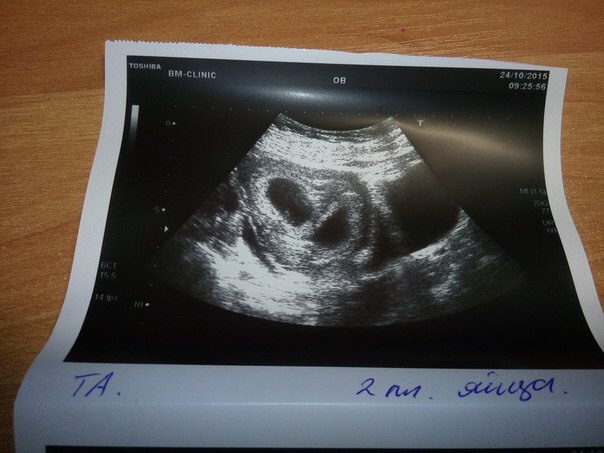

Когда я увидела вот это фото, меня словно током ударило!

Эти два маленьких человечка, которым уже 5 недель и я смотрю на них и улыбаюсь 😊